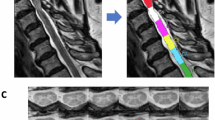

27 DCM patients were aged-matched with 20 healthy controls (HC) and categorized into treatment groups based on modified Japanese Orthopedic Association (mJOA) severity (11 mild and 16 moderate/severe). Regional and tract MTRs were extracted from the two vertebral levels containing maximum compression within magnetization transfer images. MTR differences between groups were assessed using a one-way ANOVA or Kruskal-Wallis test. The association between MTR and mJOA measures was evaluated using Spearman’s correlation.

De Leener B, Levy S, Dupont SM, Fonov VS, Stikov N, Louis Collins D, et al. SCT: Spinal Cord Toolbox, an open-source software for processing spinal cord MRI data. Neuroimage. 2017;145:24–43.

Gros C, De Leener B, Badji A, Maranzano J, Eden D, Dupont SM, et al. Automatic segmentation of the spinal cord and intramedullary multiple sclerosis lesions with convolutional neural networks. Neuroimage. 2019;184:901–15.

Cohen-Adad J, Levy S, Avants B. Slice-by-slice regularized registration for spinal cord MRI: SliceReg. Toronto, Canada: ISMRM; 2015.

De Leener B, Fonov VS, Collins DL, Callot V, Stikov N, Cohen-Adad J. PAM50: Unbiased multimodal template of the brainstem and spinal cord aligned with the ICBM152 space. Neuroimage. 2018;165:170–9.

Levy S, Benhamou M, Naaman C, Rainville P, Callot V, Cohen-Adad J. White matter atlas of the human spinal cord with estimation of partial volume effect. Neuroimage. 2015;119:262–71.